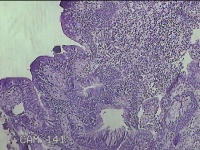

右侧鼻腔新生物

性别

女

年龄

37岁

临床诊断

1.慢性鼻窦炎 2.鼻腔新生物 3.变应性鼻炎

一般病史

鼻塞、脓涕1月。

标本名称

大体所见

灰白暗红色肿物1.3x0.7x0.3cm一个,表面光滑,切面灰白粉红色,质软。